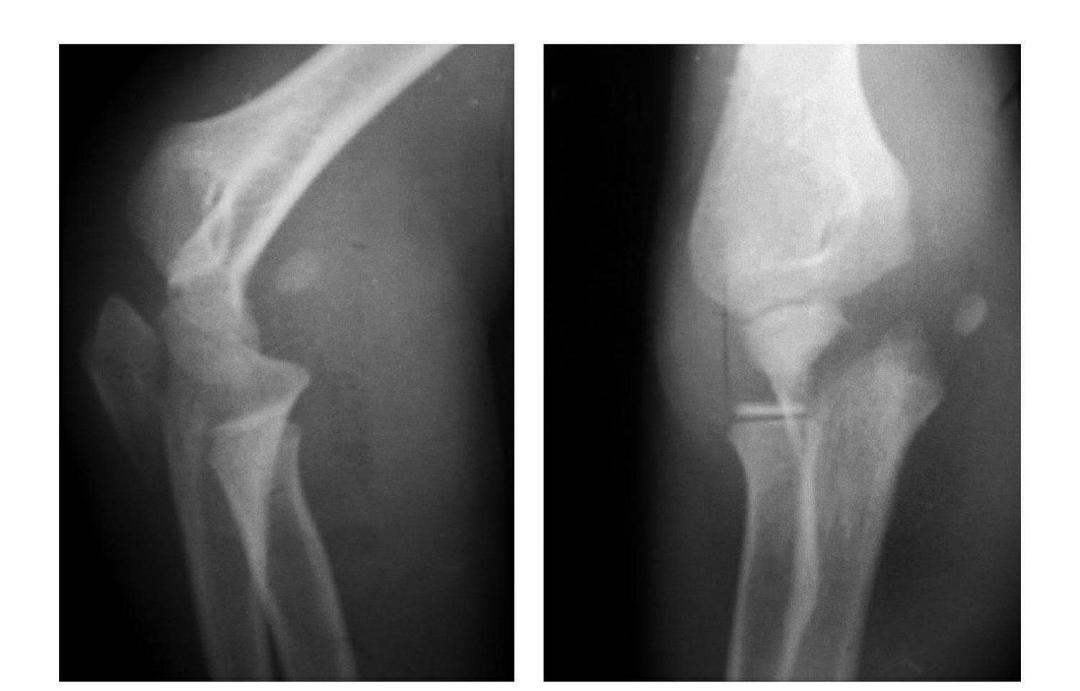

例1:肱骨小头基底部呈冠状面骨折,骨折块呈半球状向肘前上方移位。

例2:肱骨小头基底部冠状面骨折,骨折块呈半球状向肘前移位并肱骨内上髁无移位骨折。